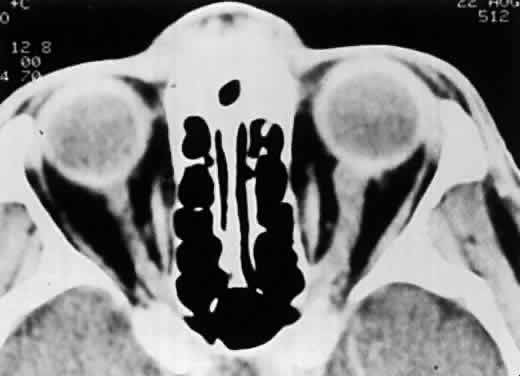

Computed tomography scans often show optic nerve sheath enlargement on the side affected with ARN.28 Bilateral optic nerve sheath enlargement has been documented despite the presence of unilateral ARN.3 Magnetic resonance imaging (MRI) has shown concurrent lesions of the optic tracts, chiasm, and lateral geniculate body in a patient with ARN, suggesting that infection may spread through the axons of the ganglion cells.3

In the absence of direct macular involvement, arterial obstruction, or retinal detachment, decreased central vision that is inconsistent with the associated retinal findings is most likely secondary to optic nerve involvement.28 The presence of optic disc swelling with ARN was noted by early investigators.10 Histopathologic studies have confirmed the presence of intraneural inflammation and necrosis.1,29–31 Both direct inflammation of the optic nerve substance and a secondary ischemic component are believed to produce ARN optic neuropathy, paralleling the pattern of visual dysfunction in the retina. When optic nerve involvement occurs in ARN, an acquired dyschromatopsia, a relative afferent pupillary defect in disproportion to the amount of retinal necrosis, central or arcuate visual field defects, and an enlarged optic nerve sheath can be detected with neuroimaging28,31 (Fig. 14). It often is difficult to distinguish whether visual loss is caused by optic neuropathy or retinal disease in these severely affected patients. An accurate assessment of the incidence of ARN optic neuropathy has not been made. Clinically, optic nerve swelling occurs in a significant number of patients with ARN and may resolve rapidly with therapy.

Fig. 14. CT scan of a patient with unilateral ARN syndrome showing enlarged left optic nerve ipsilateral to the affected eye. (Sergott RC, Belmont JB, Savino PJ et al: Optic nerve involvement in the acute retinal necrosis syndrome. Arch Ophthalmol 103:116, 1985. Reprinted with permission from the American Medical Association)